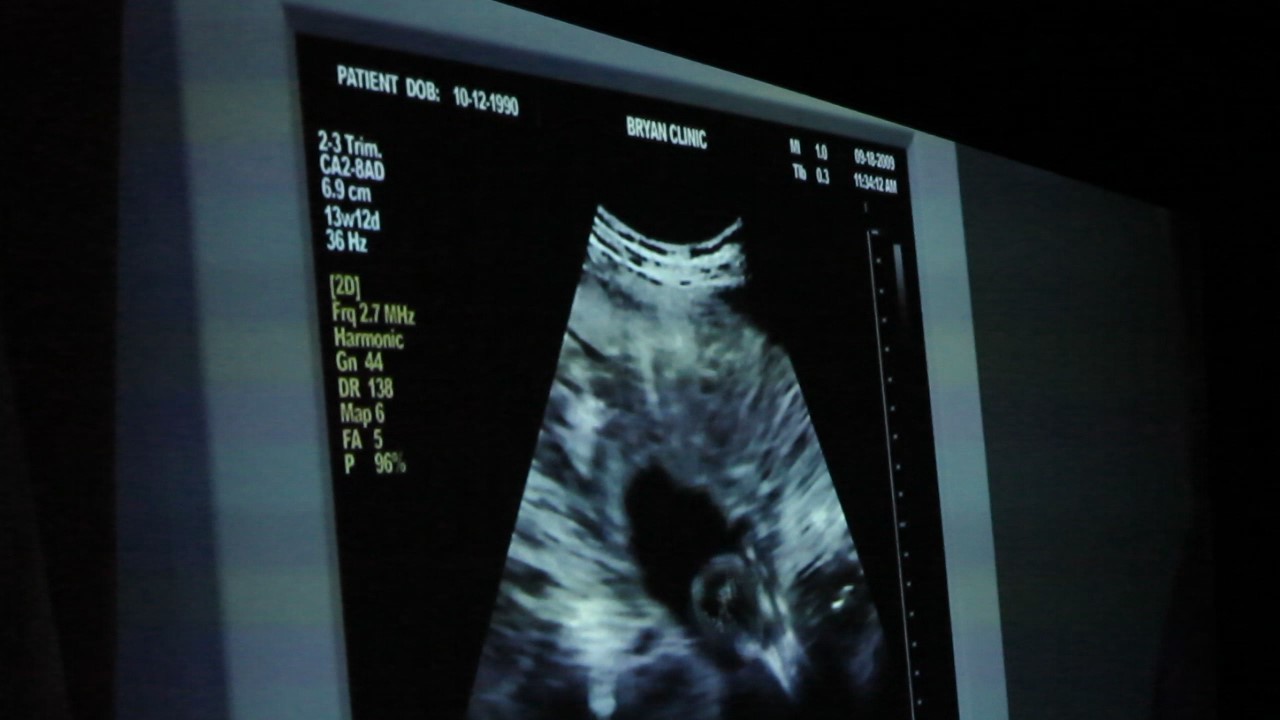

...Here is a black hole where LIFE  IS BEING SNUFFED OUT  By Abortion......  Feel THE hole BECOMING black ... DARK,    ..PITCH BLACK  ....THIS  IS a BlackHOLE  it wrenches Your stomach...as LIFE is NO More.........